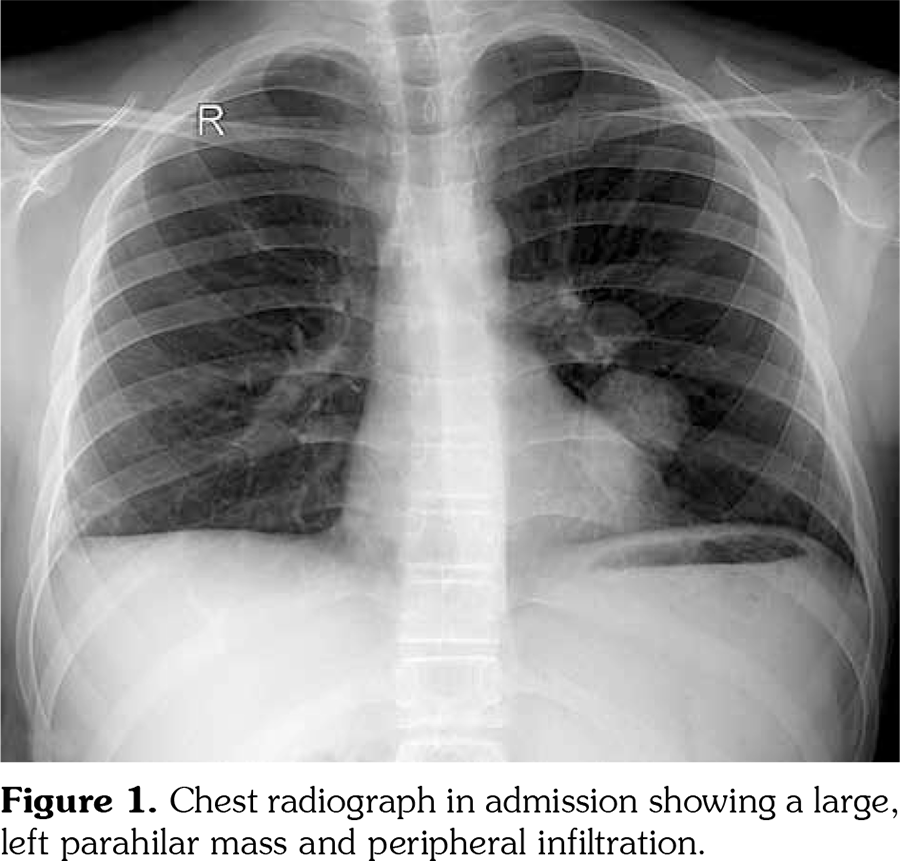

On admission, body temperature was 38.5°C. The patient had tachypnea, dyspnea, tachycardia, decrease of breath sounds in the basal regions of both lungs, and few crackling rales were heard in the left lung field. There was nearly total loss of vision in the right eye and 40% loss of vision in the left eye. Chest radiograph revealed a large left parahilar mass and peripheral infiltration (Figure 1). Computed tomography (CT) angiogram revealed two aneurysmal dilatations originating from the intraparenchymal branches of the left pulmonary artery (18x26 mm, 31x20 mm). Peripheral infarct areas were seen in basal fields of both lungs, and pulmonary embolism was present in the intraparenchymal branches of the right pulmonary artery (Figure 2). Concurrent transthoracic echocardiography showed a tripartite homogeneous hyperechogenic mass with a stalk-like structure, measuring 25x27 mm, filling most of the right ventricle, strongly suggestive of a right ventricular thrombus (Figure 3). The right ventricular pressure was within normal limits, thereby excluding pulmonary hypertension. Doppler ultrasound of lower extremities was unremarkable.